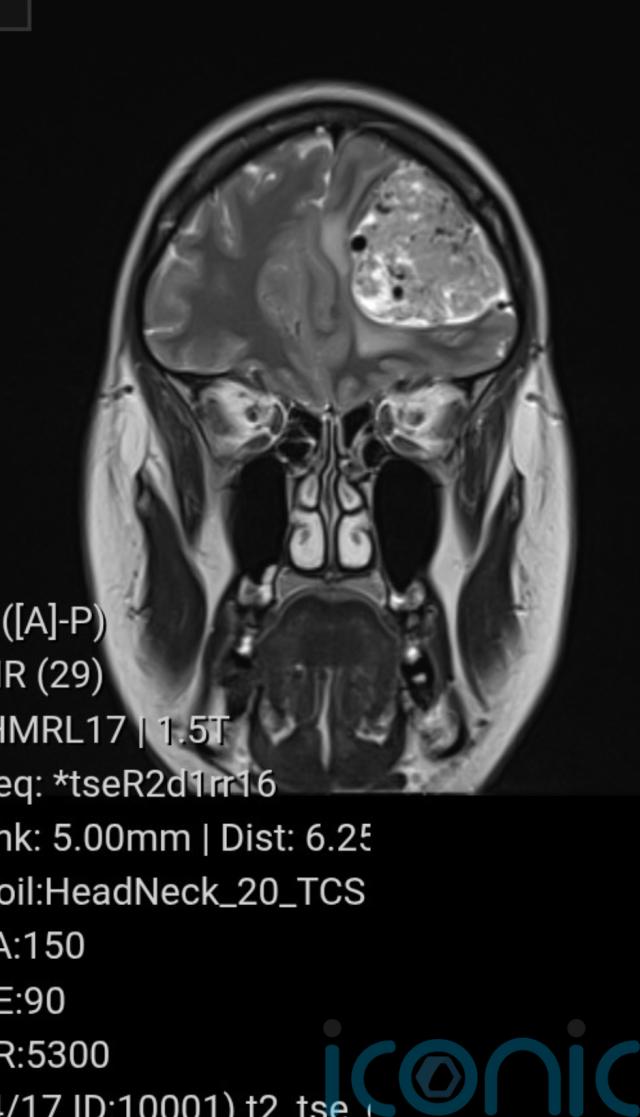

The results of her scan were sent to Medway Hospital, where a doctor informed her there was a “large mass” on her frontal lobe, which was later diagnosed as a meningioma – a non-cancerous brain tumour.

“I was shocked at how big (the tumour) was, and all the extra white stuff around it on the scan was swelling, which was causing all my head pressure.”

The tumour was diagnosed as a meningioma, and doctors suspected “it could have been growing for 20 years”.